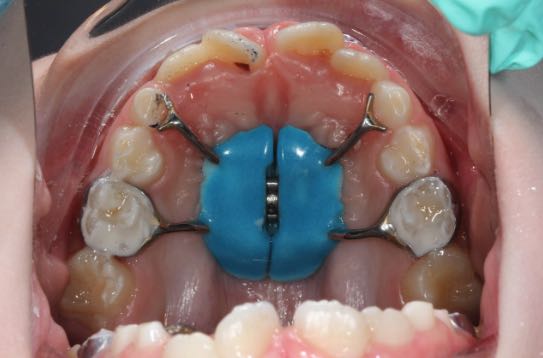

Механические

Данный вид аппаратов действует за счет сил, заложенных в него самого, и никак не зависят от действия жевательных мышц. Сила аппарата реализуется за счет винтов, пружин или дуг.